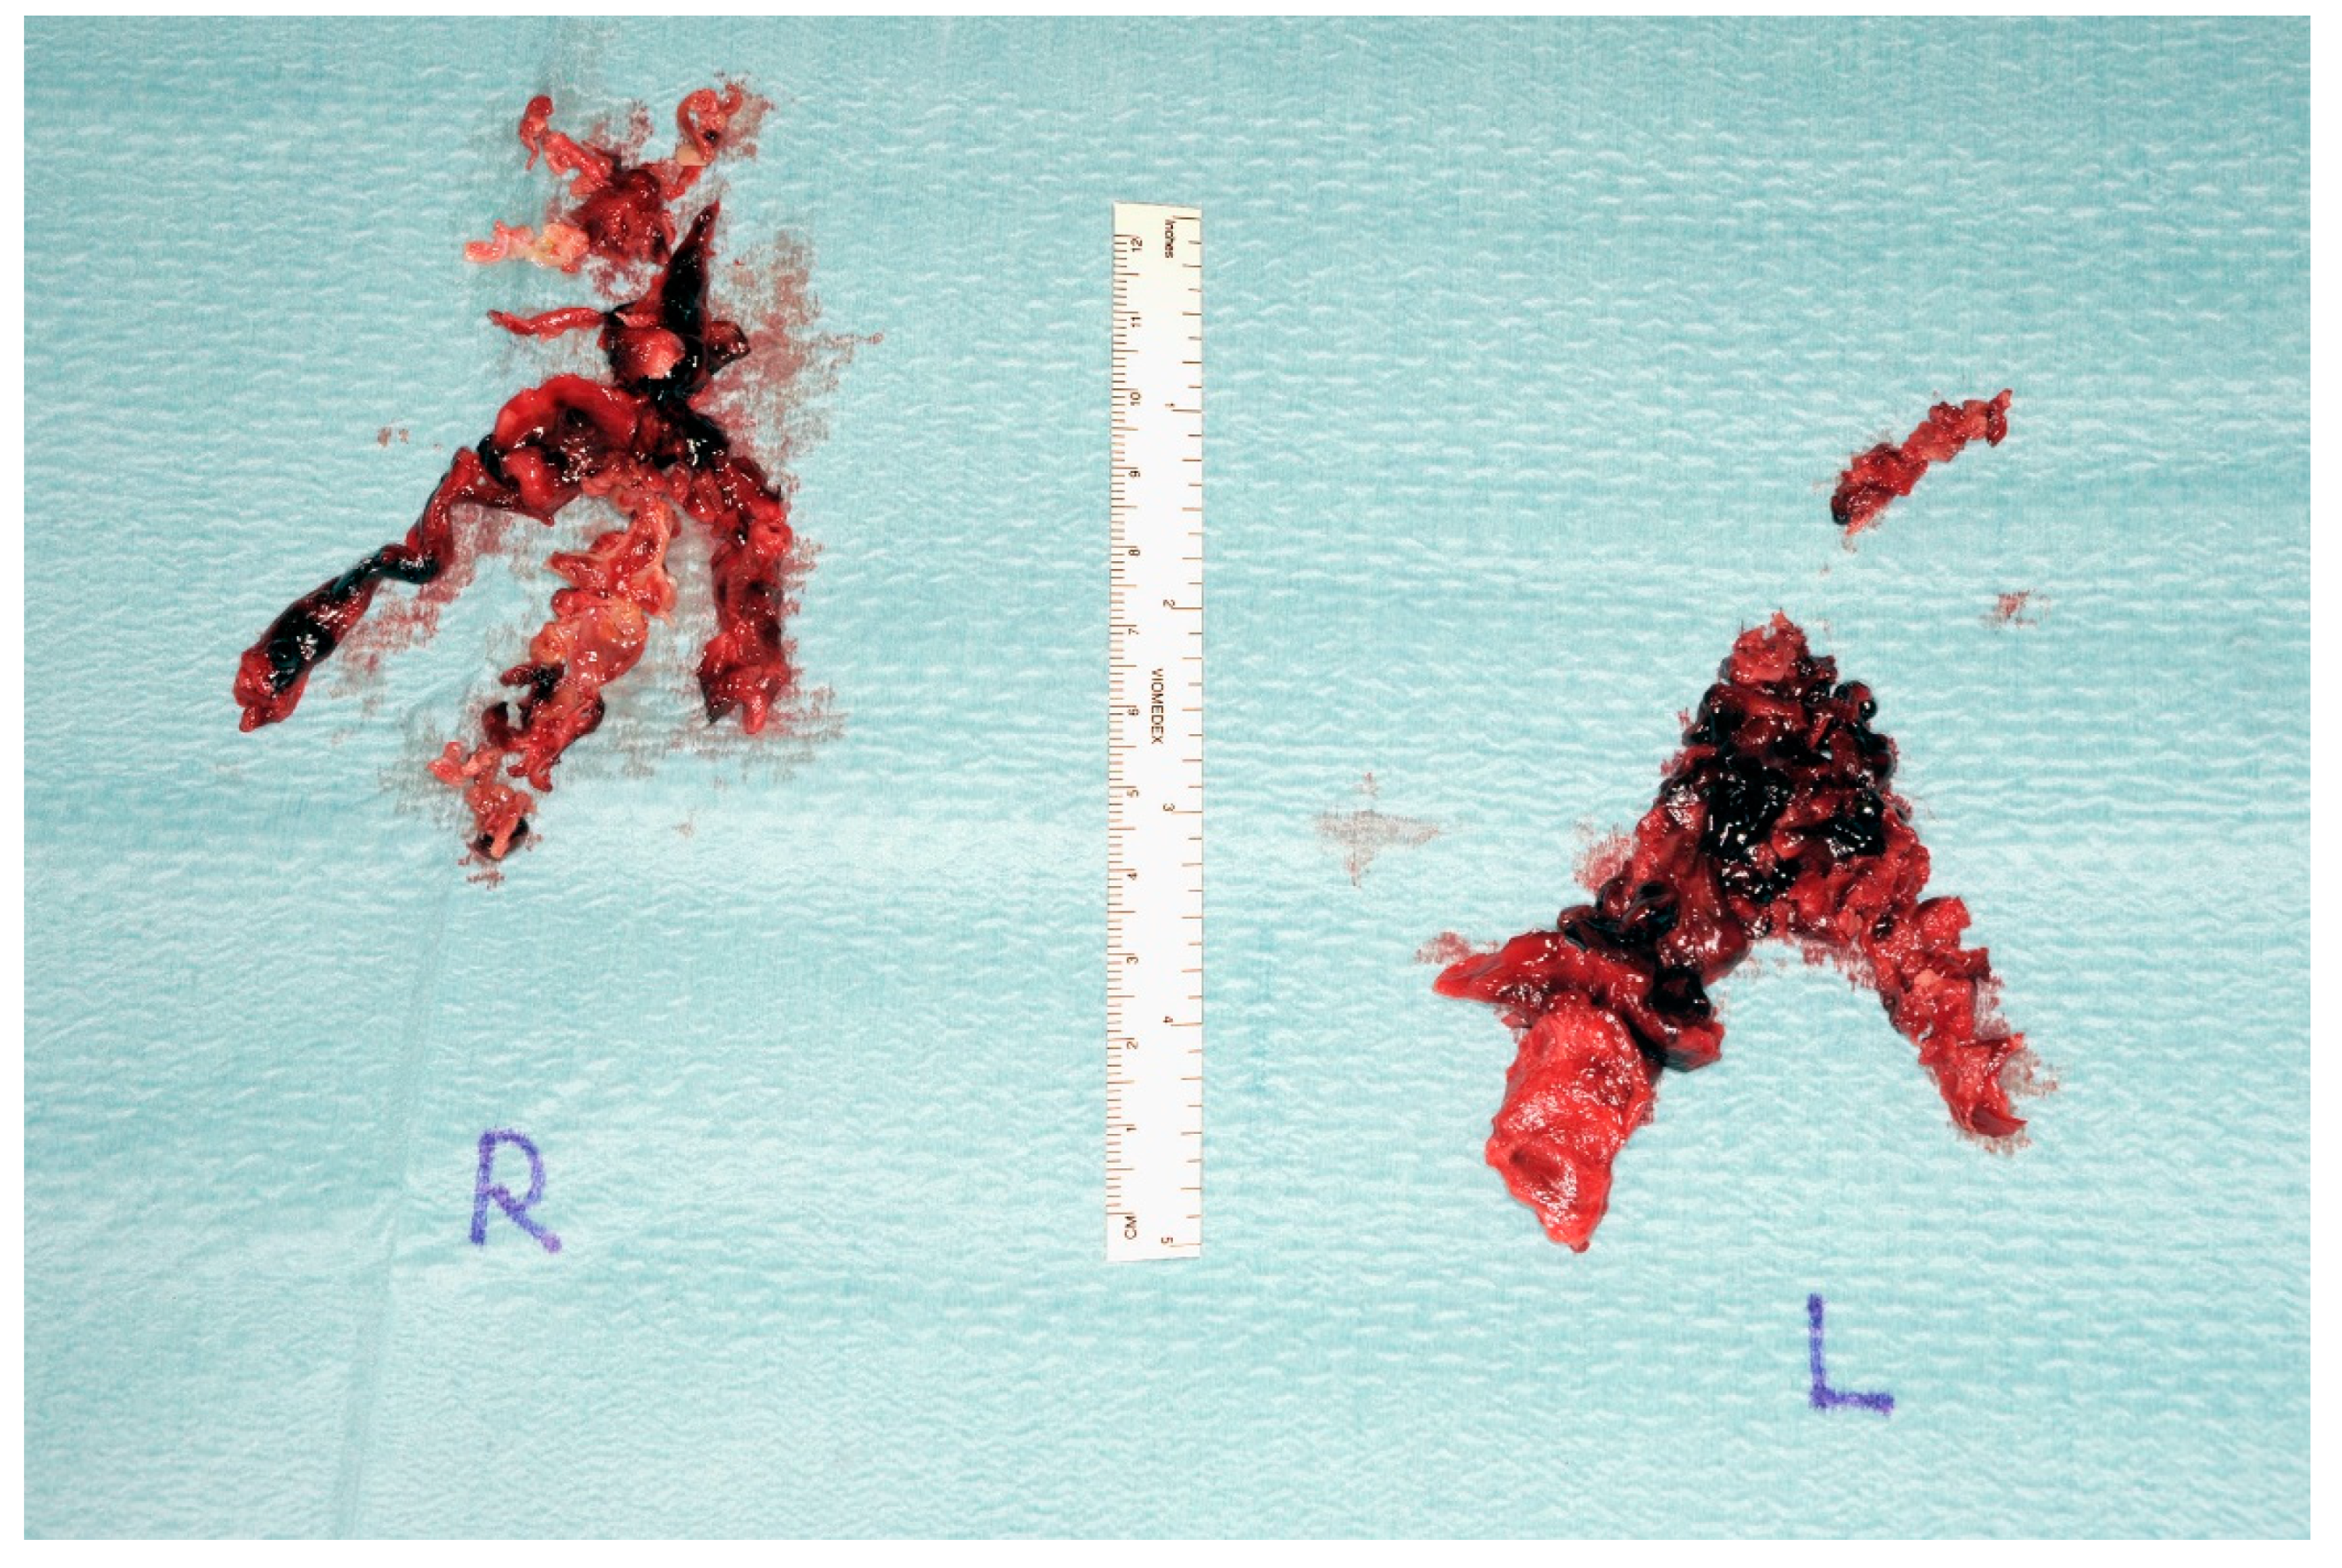

2.1. Case 1

2.2. Case 2

2.3. Case 3

2.4. Case 4